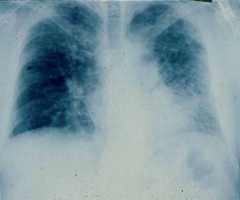

Posterior-anterior chest radiograph of a 67-year-old man with progressive dyspnea revealing bilateral reticular infiltrates with lower lobe predominance

Image: “PA chest radiograph of a 67-year old man” by Department of Medicine, Division of Pulmonary, Allergy and Critical Care, Duke University Medical Center, Durham, North Carolina 27710, USA. License:CC BY 2.0